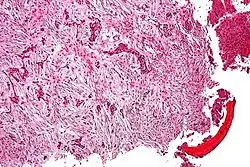

Micrograph (using H&E stain) of an adamantinoma showing the biphasic histomorphology.

Histologically, islands of epithelial cells are found in a fibrous stroma. The tumor is typically well-demarcated, osteolytic and eccentric, with cystic zones resembling soap bubbles.[2]